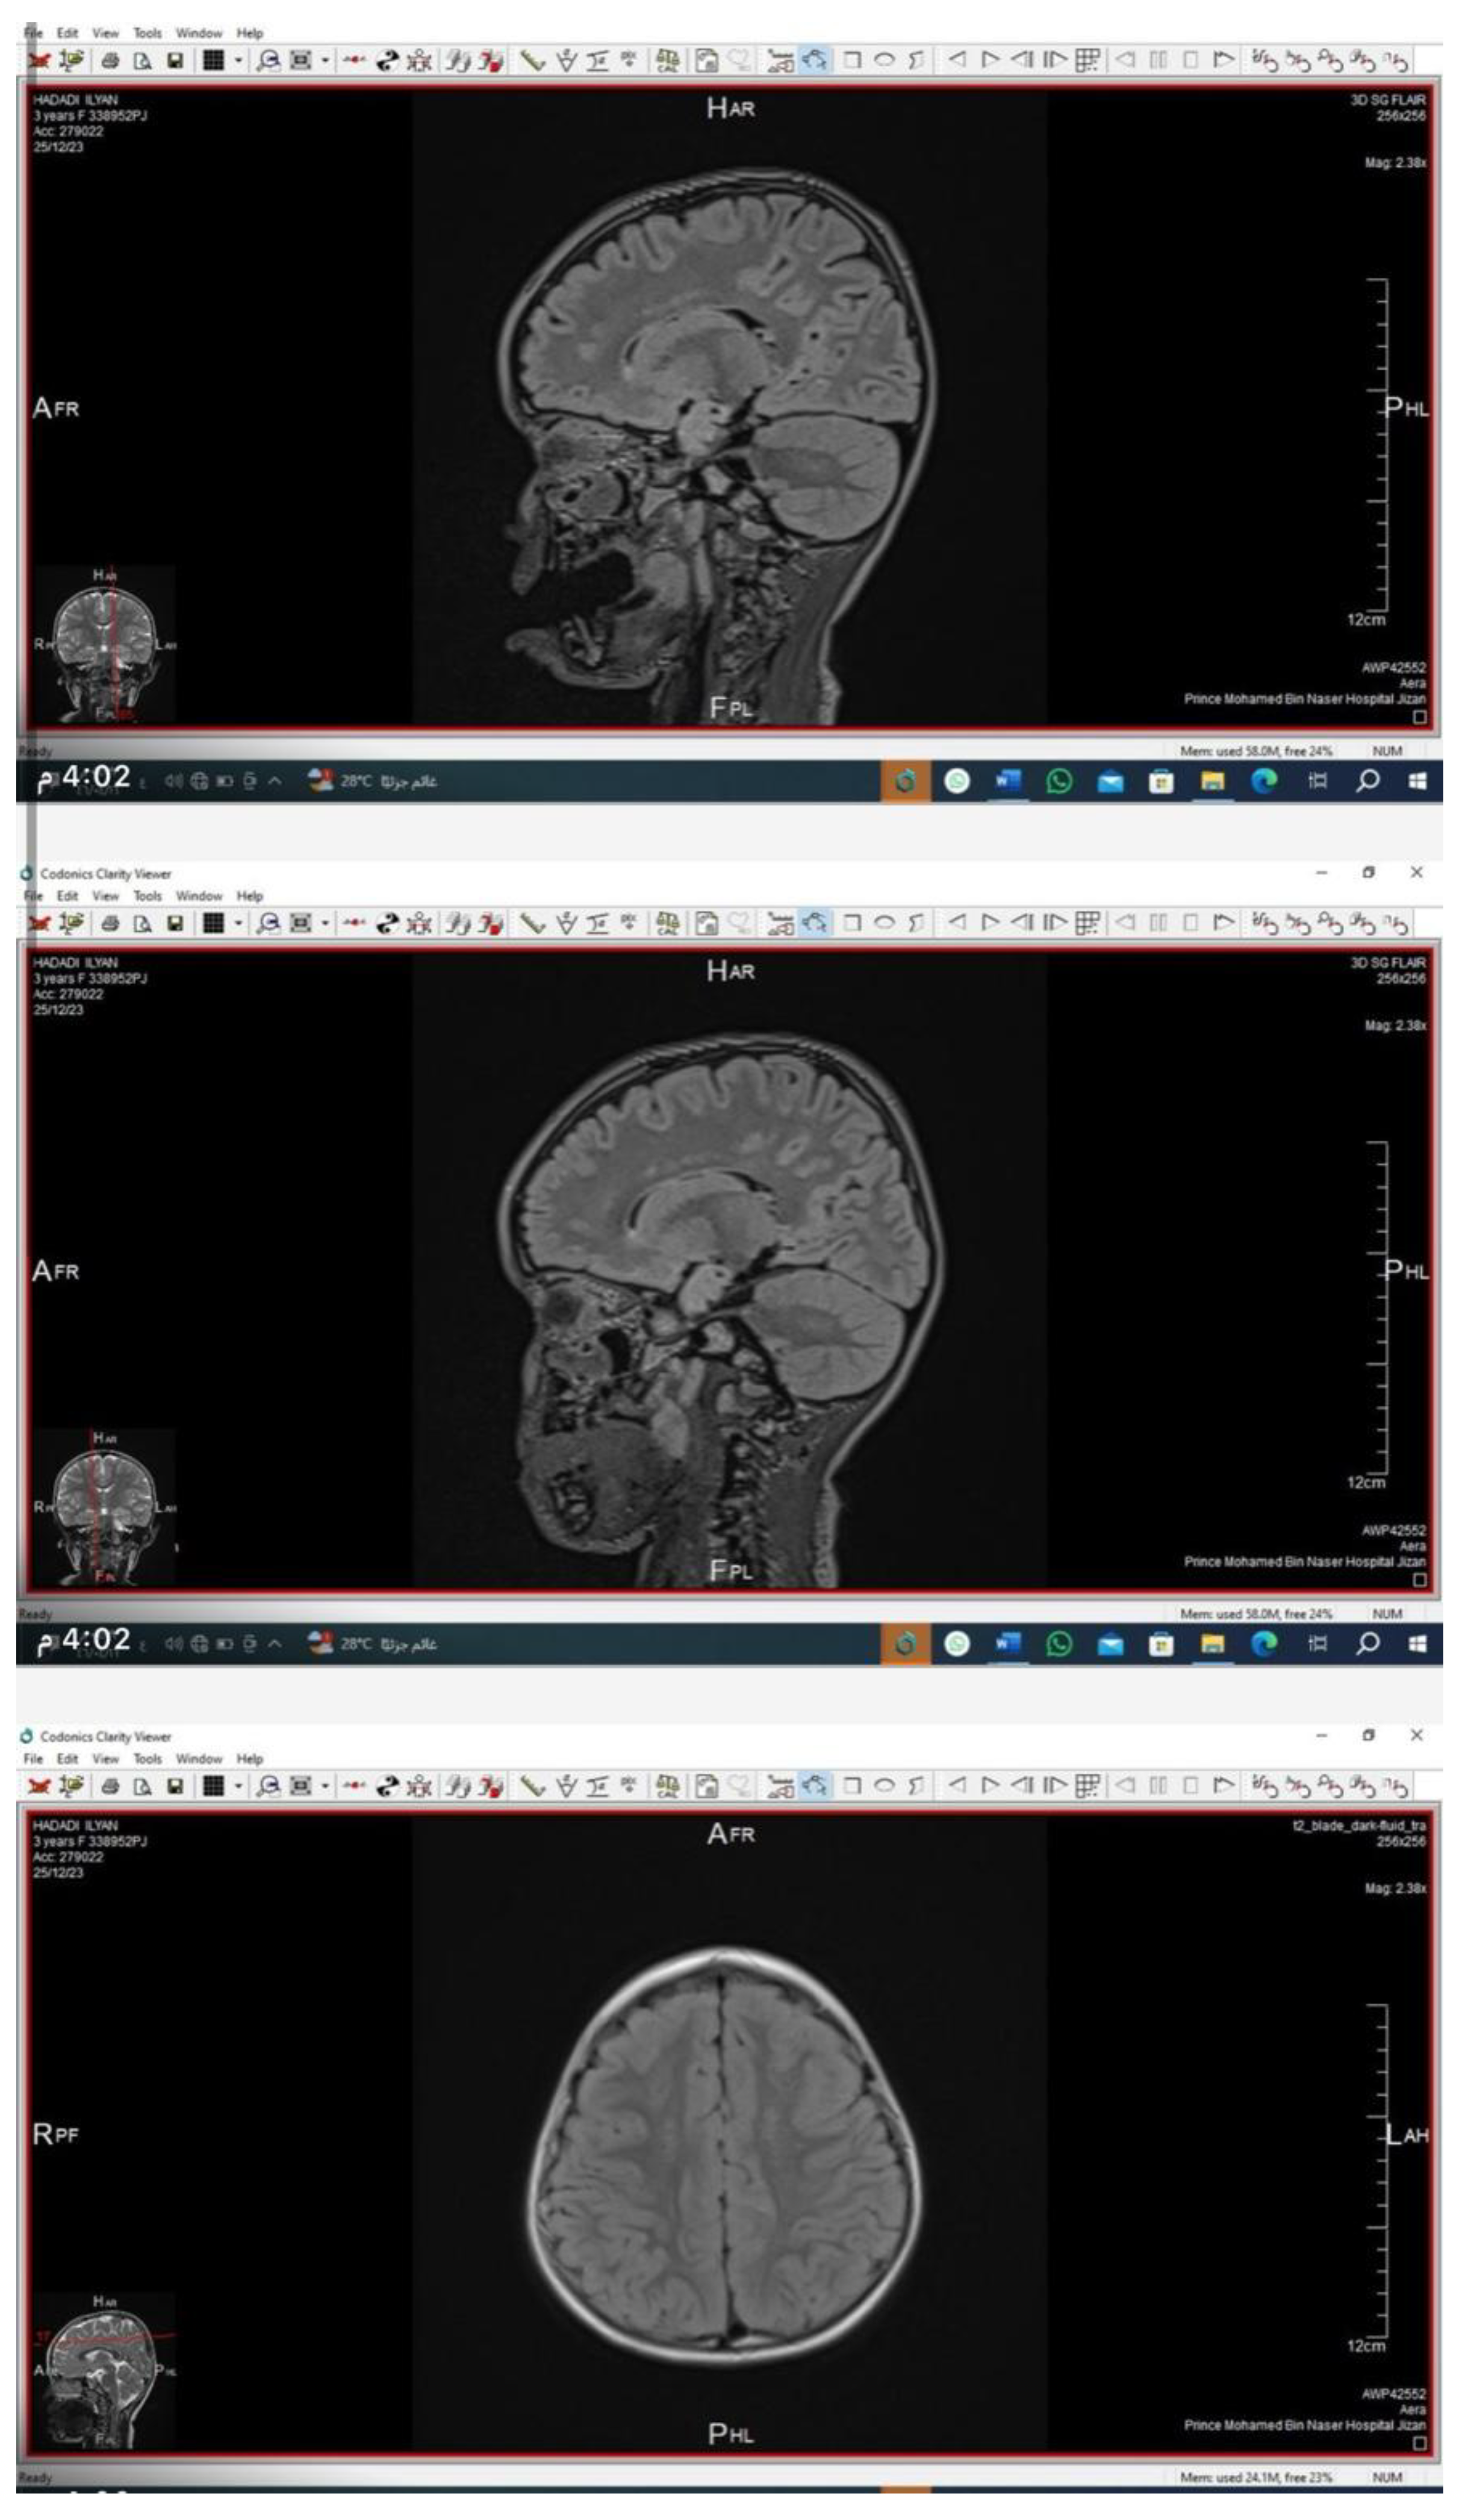

Neuroimaging

Brain and orbital MRI with contrast demonstrated bilateral, symmetrical, patchy hyperintensities in the periventricular and deep cerebral white matter on T2/FLAIR sequences, consistent with demyelination. The cerebellum and lacrimal glands appeared structurally normal.

Preprints 181080 i001

This case represents a previously undescribed CLDN10 variant associated with HELIX syndrome. The c.138G>A (p.Trp46*) mutation likely causes nonsense-mediated mRNA decay or truncation of claudin-10, leading to defective tight-junction ion selectivity. Our patient’s MRI findings are particularly noteworthy. Neurologic involvement is rarely reported in HELIX syndrome; thus, the observed white-matter changes may indicate a broader tissue distribution of claudin-10 or secondary metabolic effects.